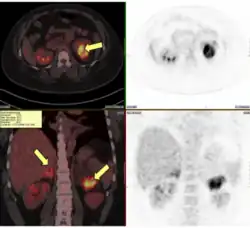

An adrenal crisis can be caused by adrenal insufficiency. Adrenal insufficiency can be classified into primary adrenal insufficiency caused by conditions affecting the adrenal cortex, secondary adrenal insufficiency due to ACTH deficiency caused by conditions affecting the hypothalamus or pituitary gland, or tertiary adrenal insufficiency caused by excessive glucocorticoid exposure. Adrenal insufficiency can be caused by autoimmune disorders such as autoimmune adrenalitis, autoimmune polyglandular syndrome, and lymphocytic hypophysitis, or congenital disorders such as congenital adrenal hyperplasia, adrenoleukodystrophy, familial glucocorticoid deficiency, combined pituitary hormone deficiency, and POMC mutation. Adrenal insufficiency can also be caused by pituitary or adrenal gland surgeries. Infections such as tuberculosis, histoplasmosis, HIV, and CMV can also cause adrenal insufficiency. Infiltrative disorders like sarcoidosis, amyloidosis, and haemochromatosis have also been known to cause adrenal insufficiency. Hemorrhages in the pituitary and adrenal glands, Waterhouse–Friderichsen syndrome, vasculitis, pituitary apoplexy, and Sheehan's syndrome are vascular disorders that can cause adrenal insufficiency. Tumors on the pituitary gland or cancer metastasis can also cause adrenal insufficiency.[10]